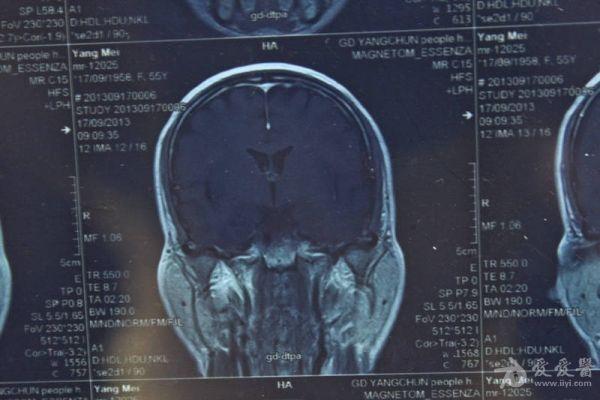

脑部占位病变CT,MRI图片,请帮忙诊断

最近感图样,无其它脑病病史

考虑脑膜瘤!!

磁共振没有平扫,增强矢状位没找到病灶。像脑膜瘤。

图片不是很清楚,应该是脑膜瘤!